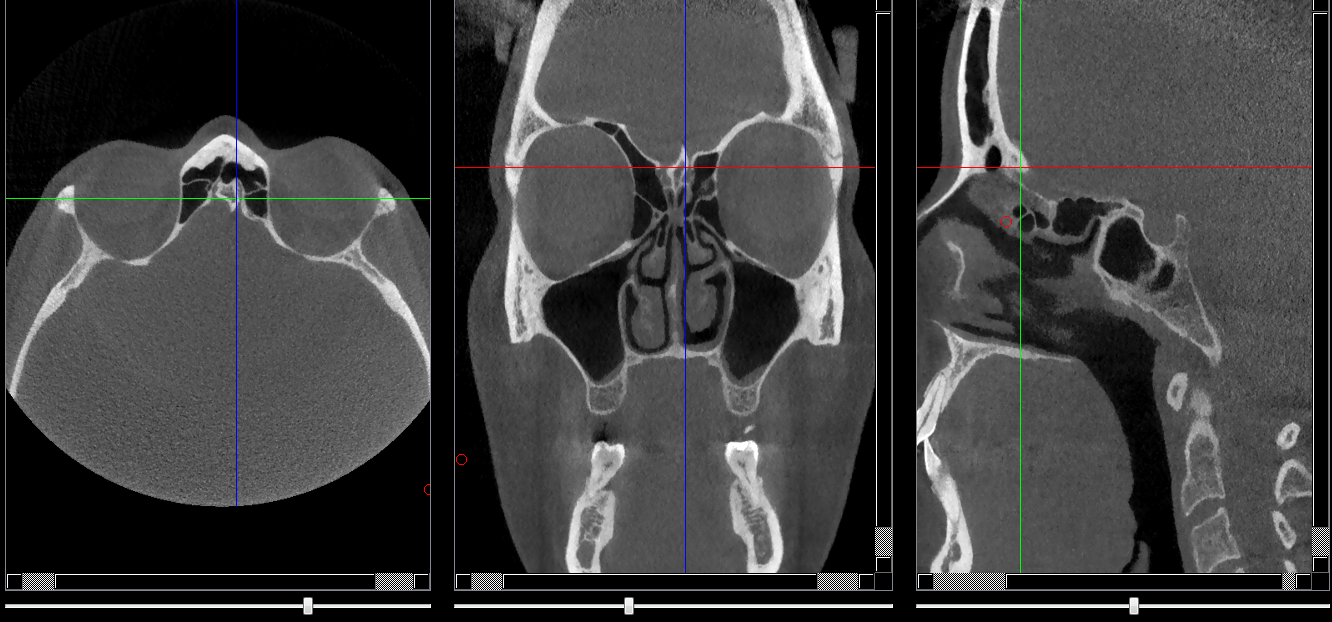

Structures osseuses

Crista galli

Repères anatomiques

- Coupe transversale

- Début : début du cornet nasal sup

- Fin : Fissure orbitaire sup

- Coupe frontale

- Début : partie post du sinus frontal

- Fin : Milieu de la lame criblée de l'ethmoide

- Coupe saggitale

- Début : Corticale interne de la portion vestibulaire du frontale

- Fin : Lame criblée de l'ethmoide

Infos sur l'image

- Auteur : Pr Bourzgui

- Co-auteur : Dr Makoure

- Affiliation : Orthopédie dento-faciale

- Date production : 2019